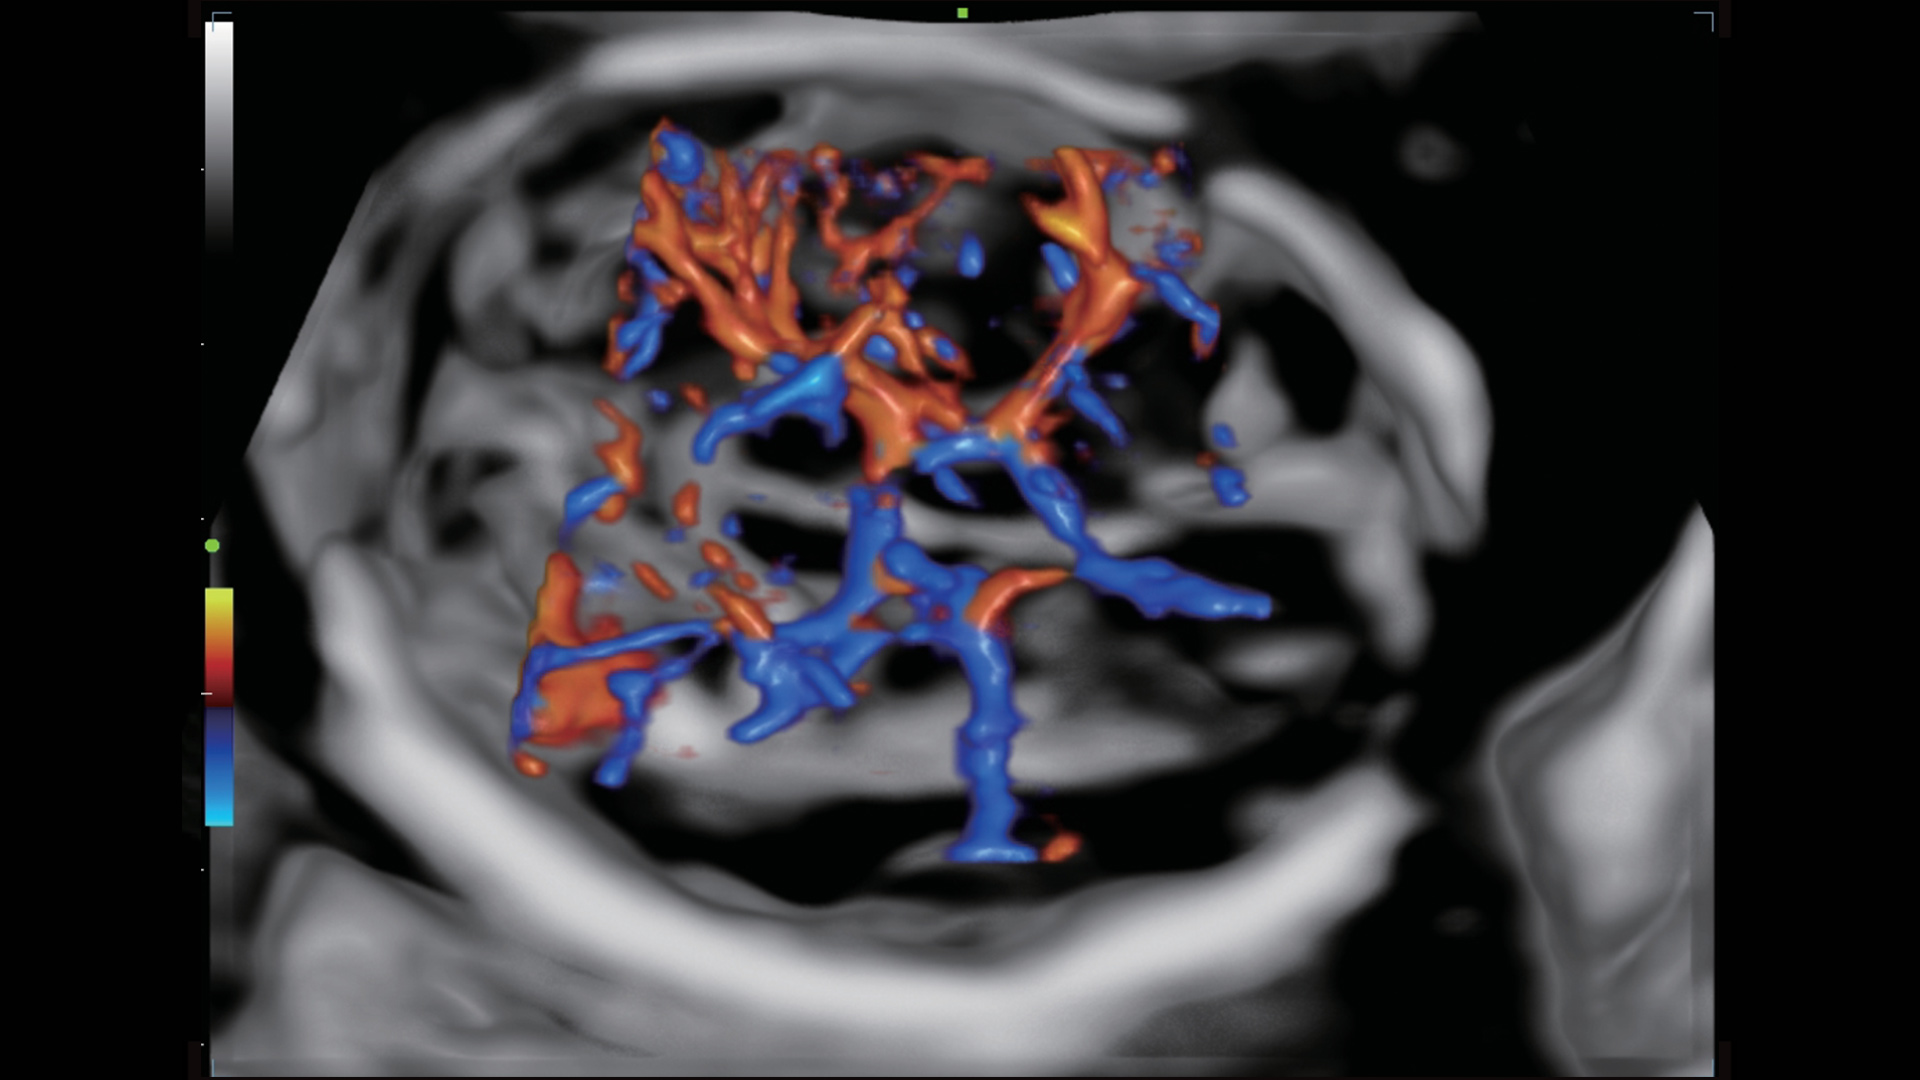

UMA (angiografia ultramicroscĆ³pica)

A tecnologia inovadora elimina as limita??es das tradicionais imagens com Doppler. Com resolu??o espacial e sensibilidade de fluxo ultra-altas, permite a detec??o de perfus?es de fluxos muito sutis e lentos, ampliando assim a aplica??o clĆnica da avalia??o qualitativa e quantitativa do ultrassom no cĆ©rebro fetal, rins, placentas, endomĆ©trios, ovĆ”rios etc.

UMA 3D ā Fluxo intracraniano do feto

UMA 3D ā Fluxo sanguĆneo perifolicular